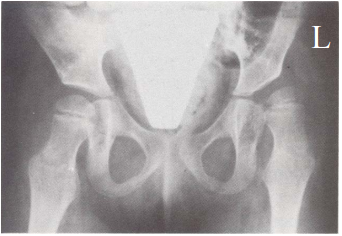

71 一位 3 歲兒童之 X 光片(如下圖),最可能是下列何種病變?

(A)左側髖關節脫臼 (B)左側股骨頭壞死 (C)右側髖關節脫臼 (D)右側股骨頭壞死